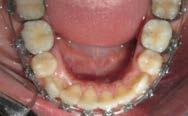

El examen clínico intraoral reveló una clase I molar bilateral, caninos superiores en infraoclusión, por ende la clase canina no se puede clasificar, presencia de apiñamiento severo, rotaciones en premolares superiores e inferiores, línea media inferior desviada hacia el lado derecho 3.5 mm,

Figura 1. Paciente femenina 15 años de edad.

falta de coordinación de las arcadas, el arco inferior con forma cuadrada y el superior forma ovoide, el overjet de 2 mm y el overbite de 2 mm (Figura 2).

Figura 2. Fotografías intraorales iniciales.